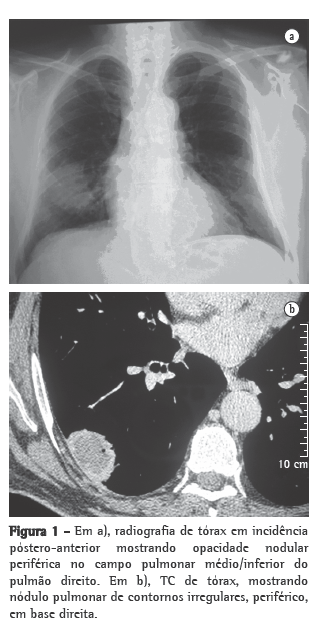

Ao exame físico, corado, hidratado, com murmúrio vesicular rude, estertores crepitantes em base de hemitórax direito, frêmito toracovocal aumentado e pressão arterial sistêmica de 120/80 mmHg. Oximetria de pulso com saturação de O2 de 96%. Foi iniciada a investigação com exames de imagem e laboratoriais. A radiografia de tórax mostrou opacidade nodular em terço inferior de hemitórax direito (Figura 1a); a radiografia de seios da face evidenciou espessamento de mucosa do seio maxilar esquerdo; e a TC de tórax, uma lesão expansiva no hemitórax direito (4,2 cm × 3,1 cm), contígua com a pleura parietal (Figura 1b). Diante disso, foi solicitada biópsia percutânea guiada por tomografia, cujo resultado mostrou áreas de fibrose e de extensa necrose associada a um processo inflamatório (Figuras 2a e 2b), cujas possíveis causas seriam: GW, granulomatose broncocêntrica ou doença infecciosa. Nos exames laboratoriais, foram encontrados: hemoglobinúria (+/4+), hematúria (29.000/mL), velocidade de hemossedimentação (27 mm/h), fator antinuclear reagente (1/40), pontilhado grosso, FR reagente (50,5 U/mL) e ANCA-c positivo. Após analisar os exames referidos, admitiu-se o diagnóstico de granulomatose de Wegener. Com a instituição do tratamento, evoluiu com melhora das manifestações clínicas e resolução da imagem pulmonar (Figura 3).

Os exames de imagem mostraram lesão nodular expansiva unilateral. Este achado é incomum na granulomatose de Wegener e, por isso, trouxe dificuldade diagnóstica diante da possibilidade de uma doença maligna. O esperado para esse tipo de vasculite seria um infiltrado pulmonar ou nódulos múltiplos bilaterais, podendo ser acompanhados de cavitações (em 50% dos casos).(8) O próximo passo, então, foi recorrer à biópsia percutânea guiada por tomografia, um procedimento que apresenta alta sensibilidade, especificidade e acurácia, esta podendo variar de 84,5% a 90% a depender diretamente do tamanho da lesão. Sua principal indicação é a pesquisa de malignidade em lesões pulmonares sólidas.(9,10)